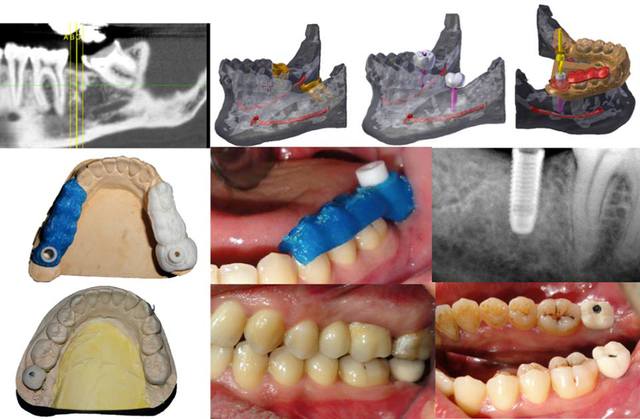

on en est a faire quelques guides et des modeles biologiques, merci a Be Open Plan, le dernier a été imprimé chez I-materialise en poly1500 matériaux biocompatible en belgique, je posterai le cas une fois terminé. en attendant on s'amuse ;)

1 ccpaxd - Eugenol

4 jqhkiq - Eugenol

8 gbcmjq - Eugenol

2 e9qnjm - Eugenol

3 y8epen - Eugenol

5 qdq4kb - Eugenol

6 kudajy - Eugenol

7 zkn7wf - Eugenol

9 ik8sfn - Eugenol